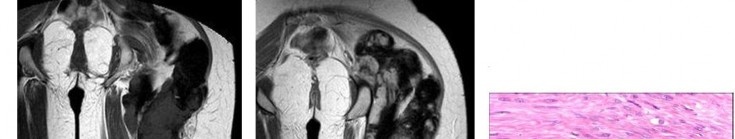

Question 17

A 35-year-old female is diagnosed with a locally aggressive giant cell tumor of the distal radius. Preoperative administration of Denosumab is planned to facilitate downstaging and joint-salvage surgery. What is the exact mechanism of action of Denosumab in this context?

Explanation

Denosumab is a fully human monoclonal antibody that specifically binds to RANKL (Receptor Activator of Nuclear factor Kappa-B Ligand). By binding to RANKL, it prevents it from interacting with the RANK receptor on the surface of osteoclasts and osteoclast precursors. In Giant Cell Tumor of bone, the neoplastic mononuclear stromal cells express high levels of RANKL, which aggressively recruits and activates the reactive multinucleated giant cells (osteoclasts) that cause bone destruction.